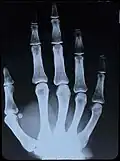

Röntgenaufnahme rechter Hand ohne Zeichnung in den Knochen im unteren Teil des Bildes -

Vorlage: Röntgenaufnahme rechter Hand;

S/W Äquidensiten erster Ordnung -